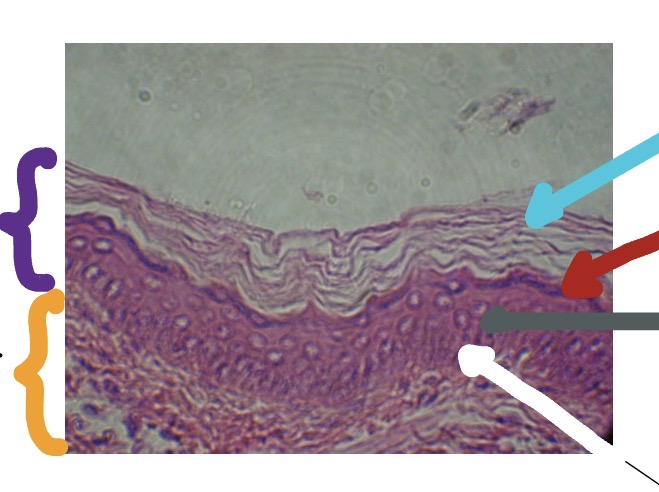

<p>What’s the yellow line in this photo</p>

Hair Shaft

<p>What the orange line in this photo</p>

Hair root

<p>What’s the dark blue line in this photo</p>

Hair follicle

<p>What’s the blue line in this photo</p>

Sebaceous gland

<p>What is the white line in this photo</p>

<p>What is the grey line in this photo</p>

<p>What is the purple line in the photo</p>

<p>What is the dark blue line in this photo</p>

Arrector Pili muscle